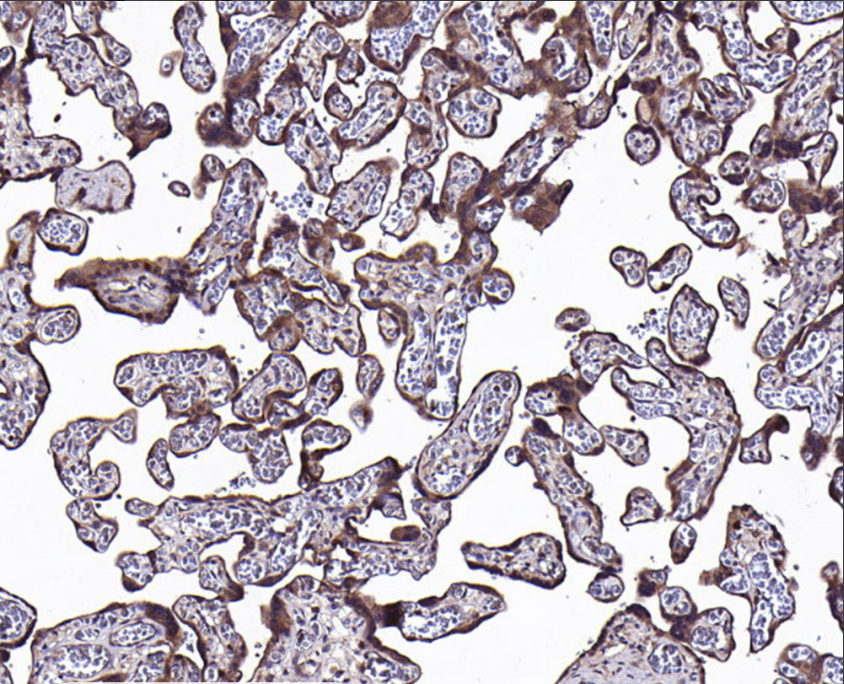

Positive control: Placenta

VEGFR-3 is the endothelial-specific VEGF-C and VEGF-D receptor for lymphatic vessels. In the embryo, VEGFR-3 can initially be expressed in all vasculature, but as the embryo develops, VEGFR-3 expression on blood vessels decreases and is confined to the endothelium of developing lymphatic vessels. In the early embryo, before lymphatic vessels emerge, VEGFR-3 acts on neovascularization; in the adult, activation of VEGFR-3 induces lymphatic vessel neogenesis. Meanwhile, VEGFR-3 mutations can lead to hereditary lymphedema.

VEGFR3 antibody reagents can specifically bind to the VEGFR3 molecular antigen. Immunohistochemistry kits containing VEGFR3 antibody reagents are suitable for the assessment of lymphatic hyperplasia diseases (such as lymphangioma) and tumor lymphatic metastasis (such as breast cancer and melanoma).